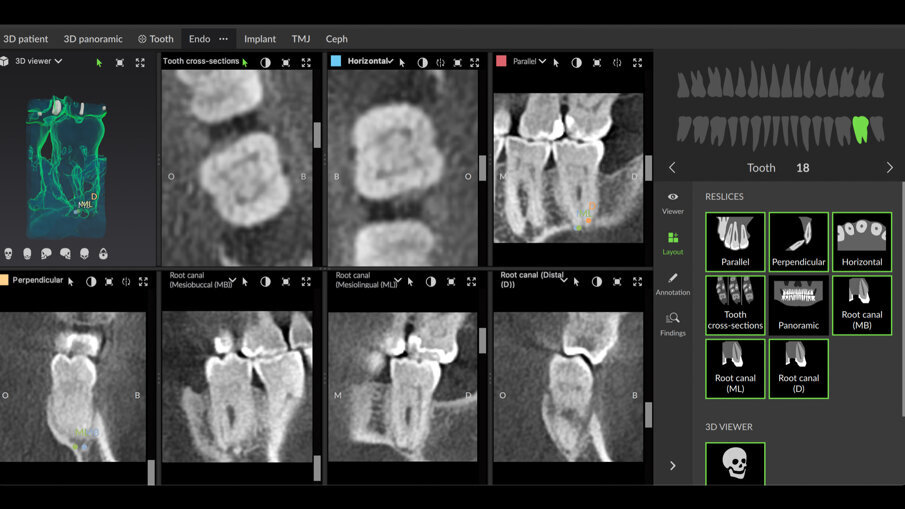

Tražio sam da se uradi i-CAT skeniranje kako bih bolje razumeo šta se dešava. Proučavajući horizontalni prikaz 3D slike, jasno se može videti nivo kalcifikacije u pulpnoj komori u poređenju sa pulpnom komorom prvog molara (Sl. 2).

Endodontski režim u novom softveru DTX Studio Clinic omogućava dodavanje mnogih pogleda i preseka i podešavanje debljine preseka kako bi se proverio nivo kalcifikacije. Dodatna prednost je što omogućava praćenje unutrašnje anatomije korena, pojedinačno i zajedno. Prilikom praćenja kanala korena, boja se može izabrati za svaki kanal. Ovo je od velike koristi za vizuelizaciju unutrašnje anatomije (Sl. 3).

Sl. 2: Horizontalni presek preuzet sa i-CAT skeniranja (DEXIS) koji pokazuje totalnu kalcifikaciju otvora kanala korena na nivou cementno-gleđnog spoja, u poređenju sa prvim molarom

Sl. 3: Endodontski režim u DTX Studio Clinic koji prati anatomiju kanala i daje približnu radnu dužinu u različitim bojama za svaki kanal